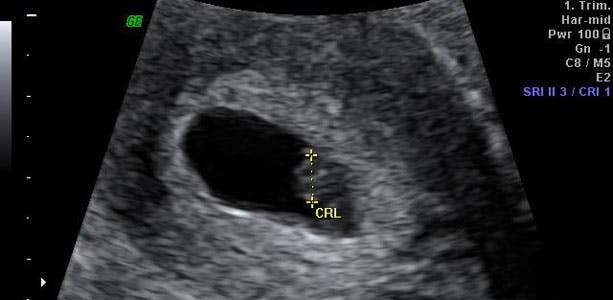

I løbet af de næste uger gennemgår din baby en intensiv udvikling, hvor følsomheden for negative påvirkninger fra for eksempel alkohol, tobak og visse typer medicin er stor. Et endnu ikke fuldt udviklet hjerte er ved at blive dannet, og omkring uge 6 eller starten af 7. uge kan du ved scanning se det slå. Fem millimeter langt og en vægt på ét gram - småt, men godt!

Fra omkring uge 6-14 angives barnets mål fra "hoved til hale" med det såkaldte crown rump length (CRL).